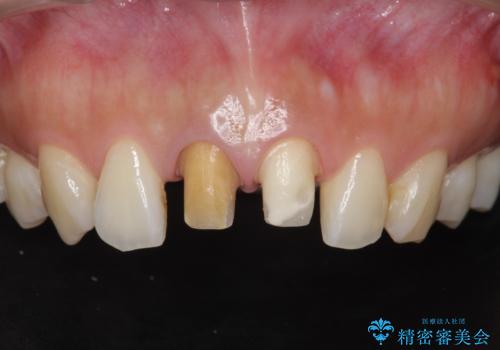

前歯の変色 根管治療と高品質セラミック歯科治療

- 前歯の変色の改善を求めて来院されました。

X線検査を行ったところ、共に深い虫歯が原因となり神経が死んでしまっている状態であることがわかり、根管治療を行ったのちセラミック補綴を行っていくこととなりました。